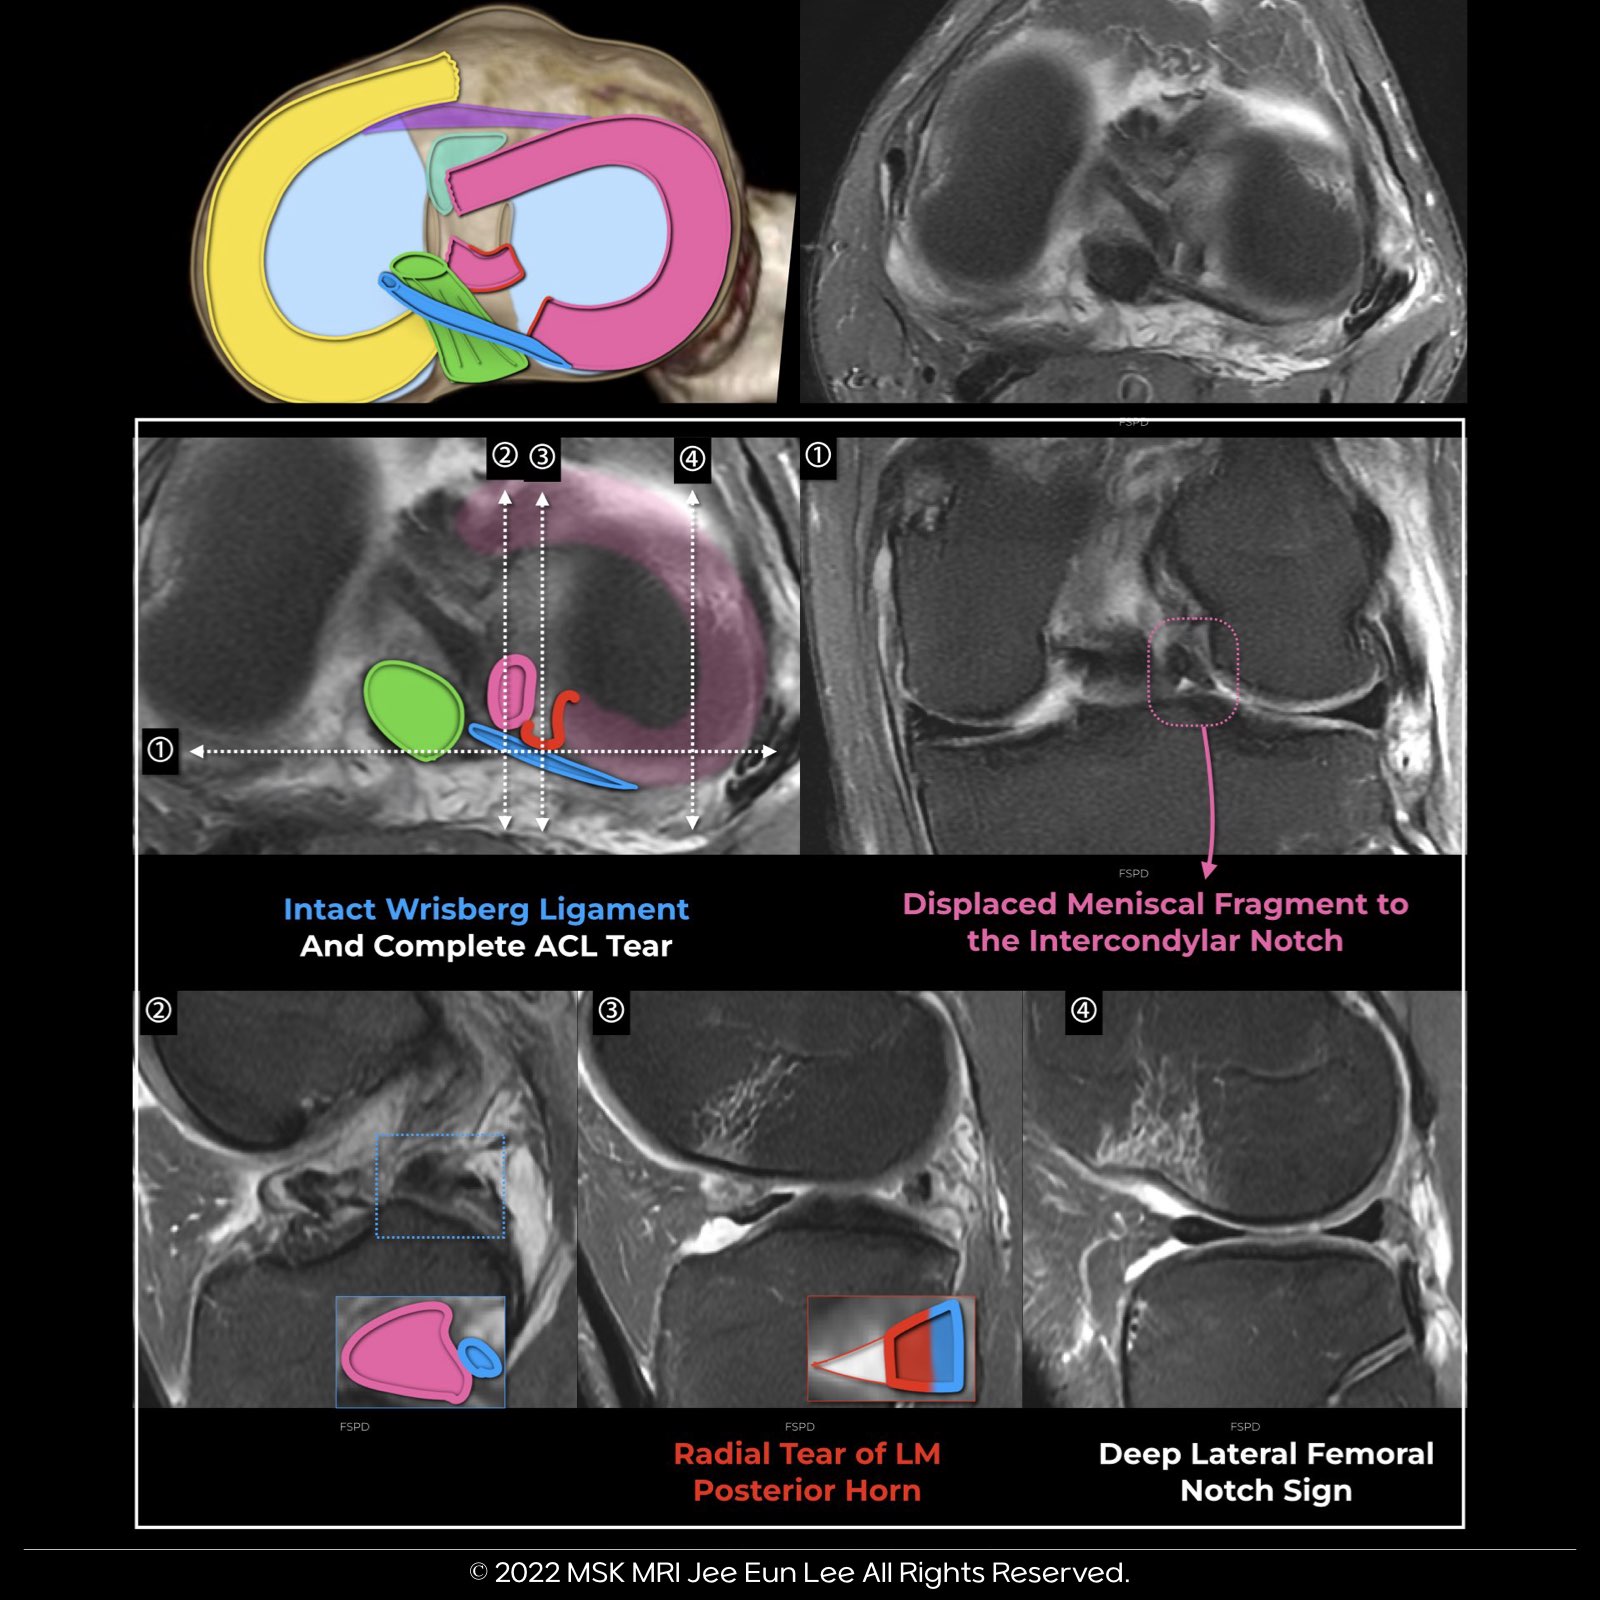

✅ Patterns of LM posterior horn tears and posterior root tears ✅

1. Wrisberg rip tear

2. Complete radial tear at the meniscus posterior horn and root junction, including meniscofemoral ligament attachment

3. Radial tear sparing the meniscofemoral ligament attachment without associated root stump displacement

4. Radial tear sparing the meniscofemoral ligament attachment with associated root stump displacement

- → Less commonly, the root stump can become inverted into the intercondylar notch, or a T-shaped oblique radial tear (with radial and longitudinal components) may involve the root region